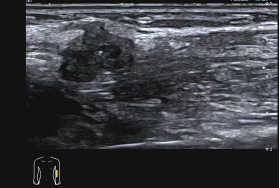

软组织肿块:鉴别软组织肿块的性质,判断是囊性还是实性,观察肿块的边界、形态、内部回声及血流情况,辅助诊断脂肪瘤、血管瘤、纤维瘤等,还可在超声引导下进行穿刺活检,明确病理诊断。